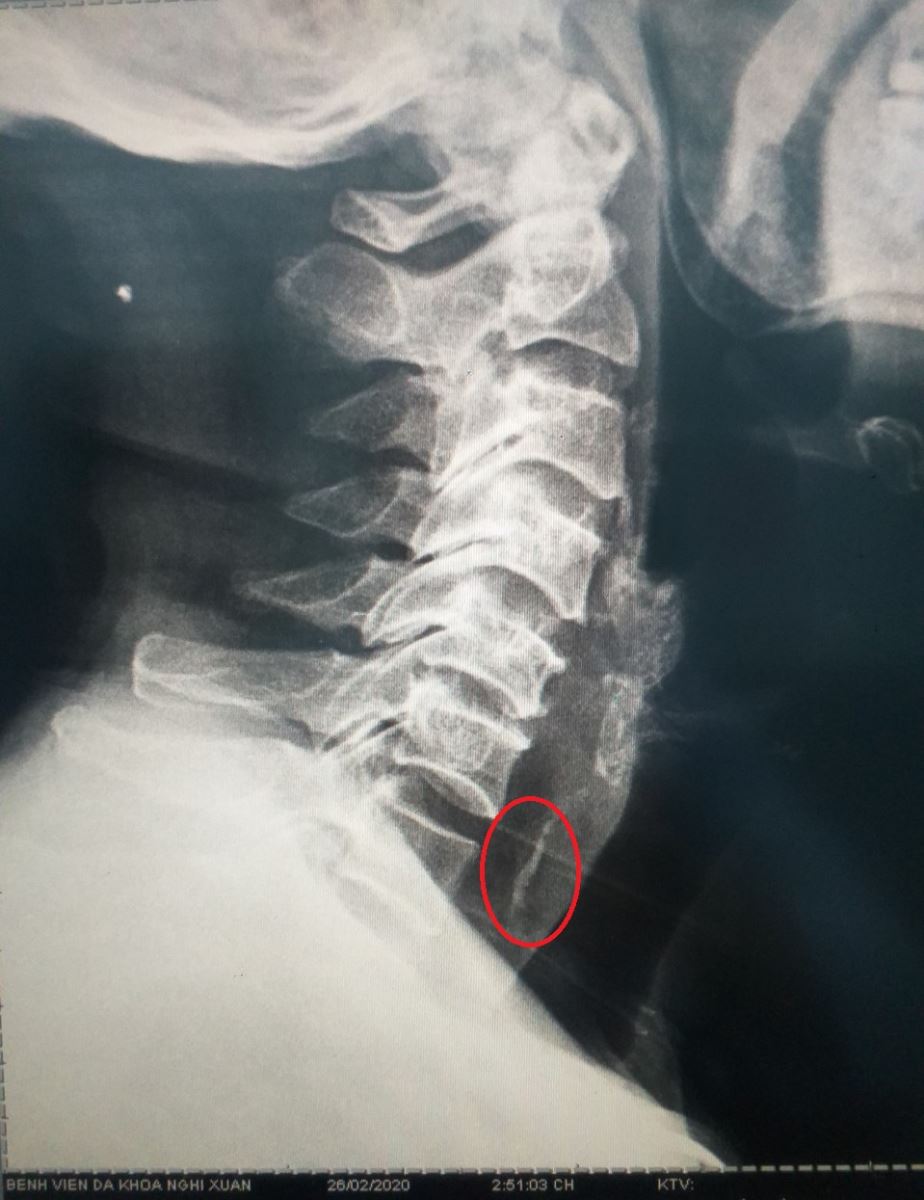

Người nhà đưa bệnh nhân đến bệnh viện đa khoa huyện Nghi Xuân. Khi nhập viện : bệnh nhân tỉnh, nuốt đau, khó nuốt, cảm giác nghẹn thở, dấu hiệu sinh tồn ổn định. Bác sỹ đã chụp X quang vùng cổ ngực thấy hình ảnh dị vật cản quang tương ứng đốt sống cổ VII và chẩn đoán: Dị vật thực quản cổ nghi hóc xương Vịt.

Hình ảnh dị vật cản quang trên phim XQ kỹ thuật số